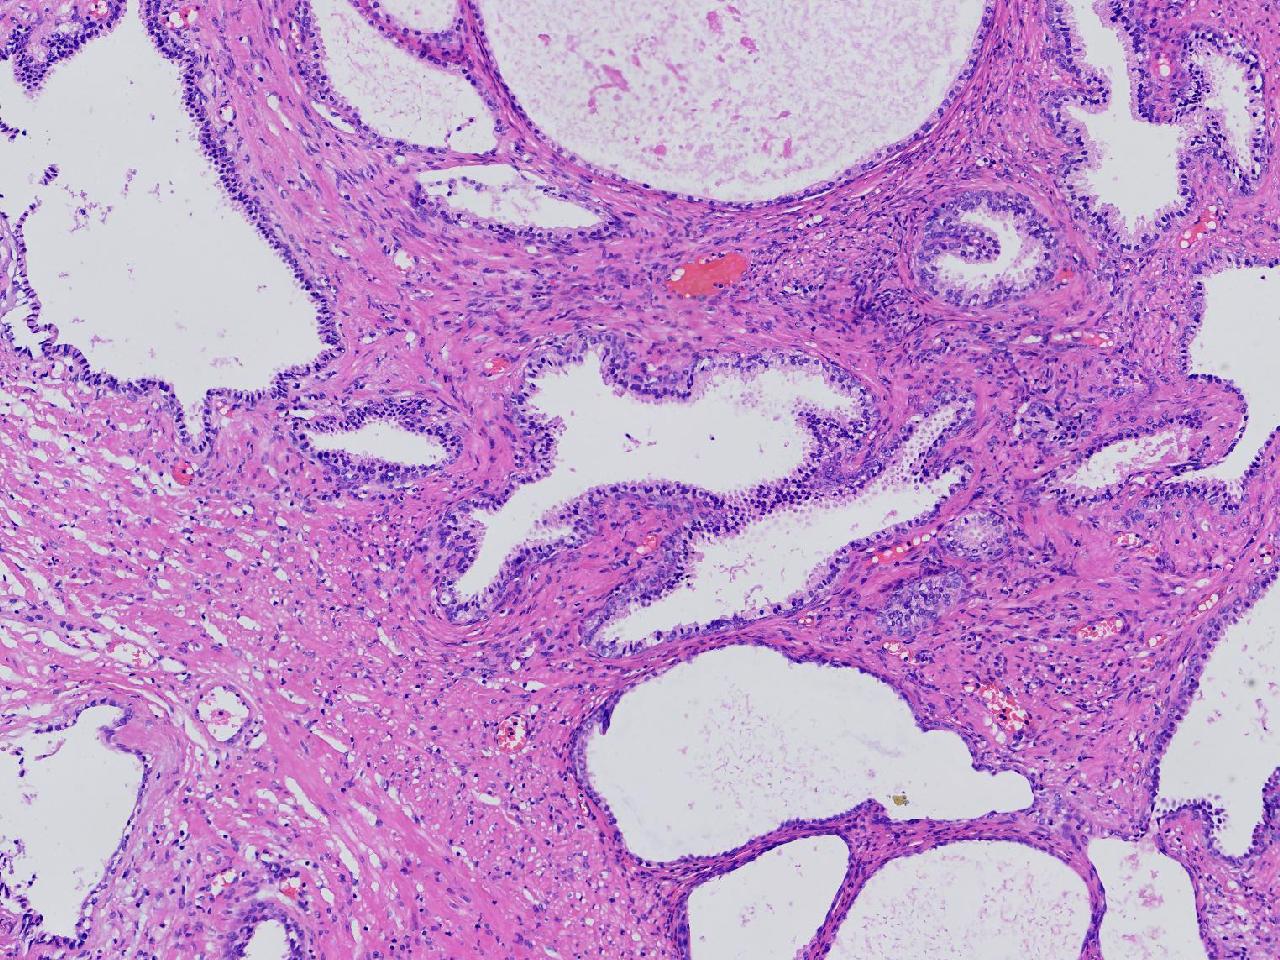

男,68岁,前列腺电切标本。

前列腺电切标本

灰粉色条索状软组织多块,5X4X3厘米。

前列腺增生。

BPH.